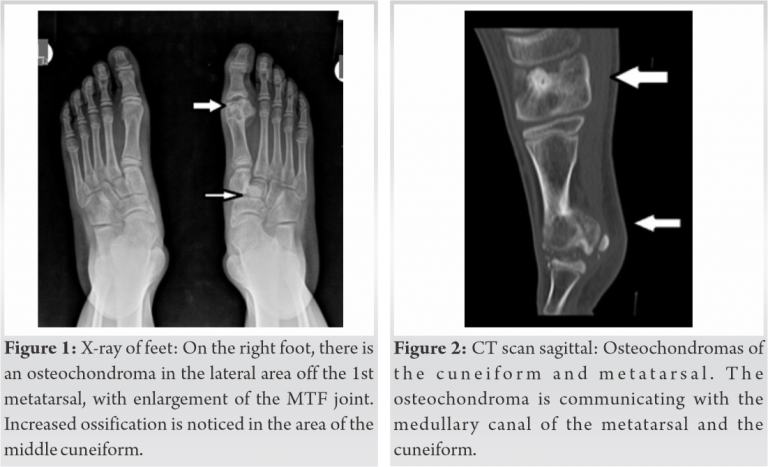

A young adolescent attended our outpatient department seeking advice on the unusual growth of his left foot. He was a healthy and active young boy, without other underlying pathology. He reported pain during daily activities, in particular while playing football. He was wearing shoes that were larger in size than anticipated for his body. On clinical examination, there was a marked prominence in the medial and plantar arch of the foot and the plantar area of the 1st metatarsal. The foot had minor skin sclerosis in the area of the 1st metatarsal. On palpation, two firm solid masses were found, one plantar and lateral to the head of the 1st metatarsal and the other in the plantar surface of the cuneiforms. No other prominences were found in the skeleton. His ability to tip toe and jump on his left foot was limited. He expressed discomfort in the passive movements of the 1st MTP joint. Plain X-ray revealed two distinct well delineated tumors. They both had marked calcification, extending in the plantar surface. One was located in the head of the 1st metatarsal and the other in the area of the cuneiforms. The tumor of the 1st metatarsal was protruding plantar and lateral. It extended to the 1st MTF joint, with enlargement of the joint. The growth plate of the metatarsal and of the proximal phalanx was not affected. The other tumor found on the cuneiform appeared as an osteosclerotic lesion with minimal widening of the joints between the cuneiforms. A computed tomography (CT) scan was performed confirming the presence of two giant osteochondromas. The first was arising from the 1st metatarsal, communicating with the metatarsal bone. The medial sesamoid was articulating with the osteochondroma, in the plantar area.

The second osteochondroma was found in the area of the cuneiforms, with clear borders. It was communicating with the medial cuneiform, distorting the normal relation of the cuneiforms with the navicular and the metatarsals.